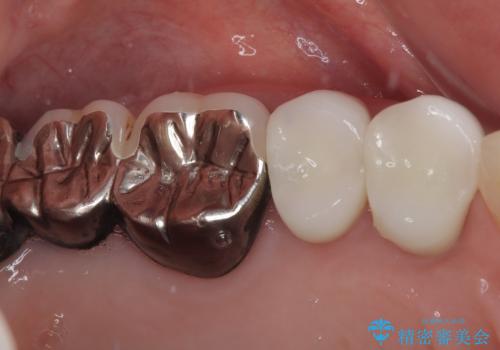

黄ばんできてしまった小臼歯部のクラウンは、根尖部に症状を認めないため、そのままオールセラミッククラウンによる補綴治療を行うこととしました。